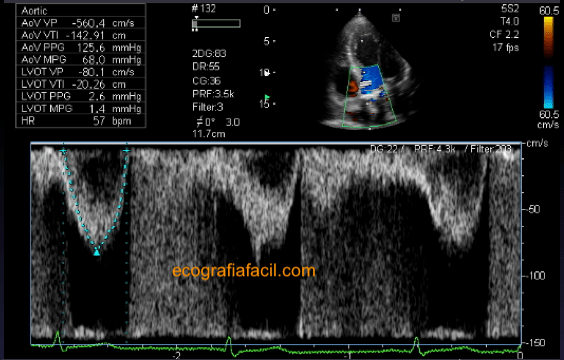

Otra medida que vamos a hacer en este plano será el cálculo del área valvular para lo que nos basamos en la “ecuación de continuidad”. Para ello necesitamos sacar la integral velocidad-tiempo en el tracto de salida del VI (TSVI) con Doppler pulsado (figura 22) y los gradientes máximo y medio transvalvulares aórticos con Doppler continuo (figura 23). Mediante estas dos mediciones y la que ya teníamos antes del diámetro del TSVI, que habíamos medido en el paraesternal eje largo, podremos calcular el área y cuantificar el grado de severidad en caso de estenosis.

Another measure that we are going to do in this plane will be the calculation of the valvular area for what we rely on in the «continuity equation». For this, we need to take the velocity-time integral in the LV outflow tract (LVOT) with pulsed Doppler (figure 22) and the aortic transvalvular maximum and middle gradients with continuous Doppler (figure 23). By means of these two measurements and the one that we had before the diameter of the LVOT, which we had in the parasternal long axis, we can calculate the area and quantify the degree of severity in case of stenosis.

Fig 22

Fig 23